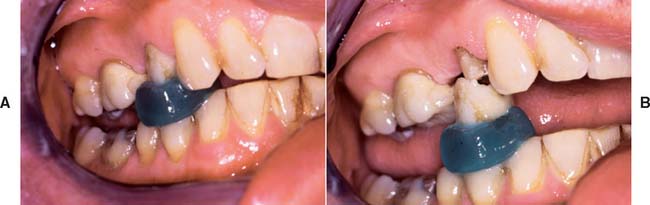

Fig. 32-42 This patient presented with multiple failing restorations and severely compromised function (Treatment X). A to E, Preoperative photographs. F to J, Posttreatment photographs. Where possible, I-bars were used to minimize clasp visibility. Also note the extensive use of metal occlusal surfaces. When prostheses are designed for dentitions with compromised crown/root ratios, precise adjustment of the occlusion and anterior guidance components is critical. K to Q, Seventeen-year follow-up photographs. Note that the maxillary canine was lost and the existing retainer was modified into a pontic through the addition of composite resin. Additional endodontic treatment was needed as time passed. R, Preoperative radiographs. S, Postoperative radiographs. T, Eight-year postoperative radiographs. U, Seventeen-year postoperative radiographs. A fixed dental prosthesis (FDP) was fabricated, replacing the missing tooth #3 with teeth #5, #4, and #2 as abutments. The teeth were prepared with minimal taper, and the castings exhibited good retention. After 10 years, the FDP failed when tooth #2 became dislodged, possibly as a result of the additional loading by the removable dental prosthesis (RDP). Tooth #2 and the pontic were removed, endodontic treatment was performed, a new crown was fabricated, and the #3 pontic was incorporated in a new RDP. Tooth #6 was lost as a result of internal resorption and caries. Initially, the tooth was discolored, but the lesion was inactive, and the attempt to save it failed after 8 years. Its guarded prognosis was discussed as a significant risk factor before treatment initiation. This suggests that teeth with a guarded prognosis can be maintained if attention is paid to the principles of casting adaptation and occlusion.